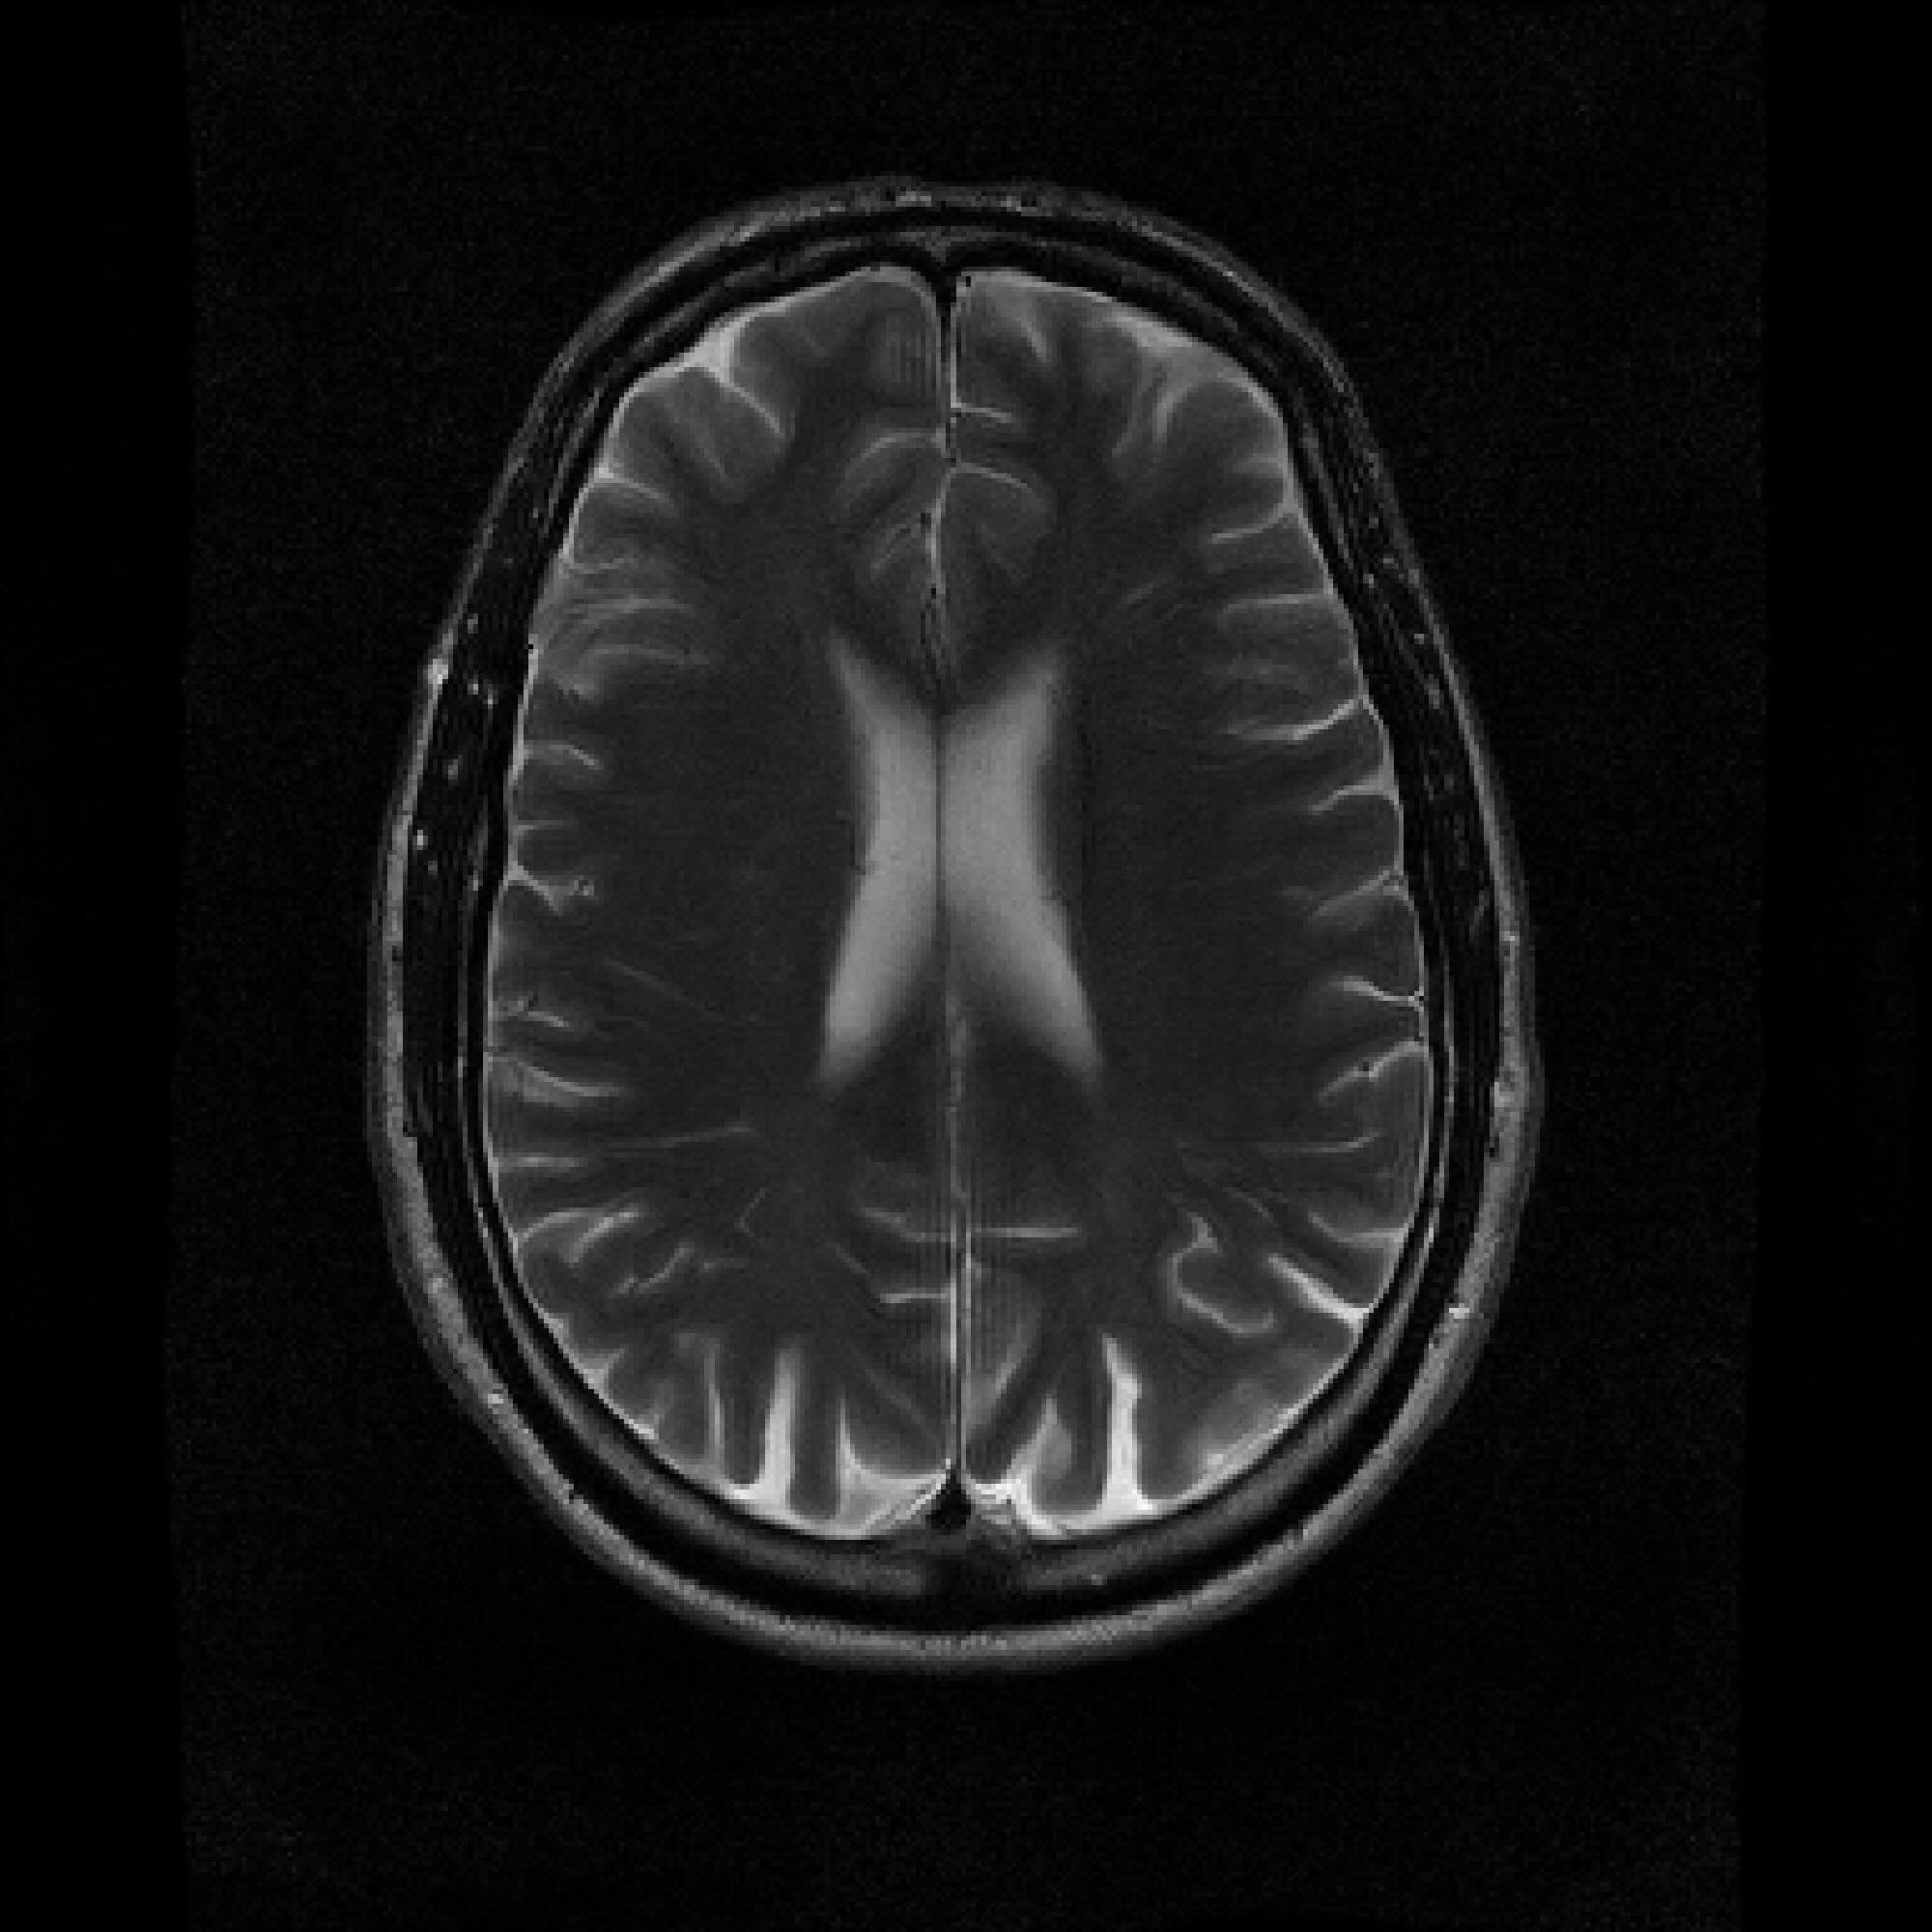

Figure 2: Example MRI magnitude reconstructions with S=25S=25 training slices at acceleration factor R=7R=7. PaDIS-MRI reconstructions are sharper and more faithful to the fully-sampled ground truth. Insets are shown to highlight detail.

Figure 2 provides a visual comparison of the reconstruction quality of each method on example slices. In reconstructions from the S=25,R=7S=25,R=7 models, FastMRI-EDM exhibits slightly more blurring and loss of fine structural details, particularly in regions with complex anatomical features. PaDIS-MRI, in contrast, preserves sharper boundaries and finer details. This enhanced data efficiency can be attributed to the patch-based prior’s ability to learn localized structural motifs more effectively from limited examples. Figure 6 in the Appendix shows similar reconstructions at S=200,R=7S=200,R=7 where FastMRI-EDM more closely approaches the performance of PaDIS-MRI but still struggles with highly detailed anatomy. At both dataset sizes, MoDL underperforms the diffusion priors. In Figure 2, MoDL’s FLAIR reconstruction exhibits pronounced artifacts, likely reflecting reduced generalizability of a supervised prior when the training distribution underrepresents FLAIR.